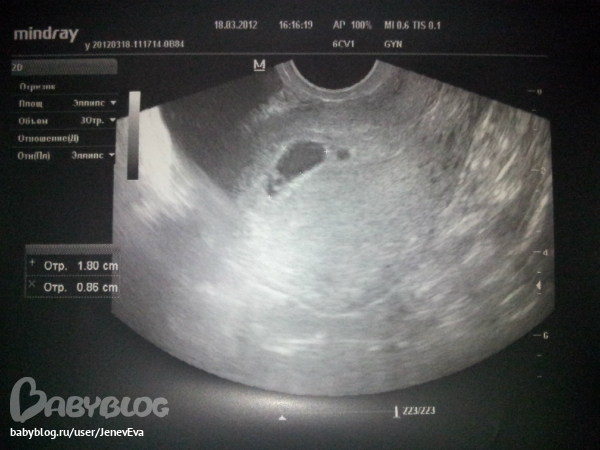

Может кто сталкивался с такими вот картинами на узи? Врач поставила диагноз что отслоение какое-то, но так же сказала что может быть и многоплодная была но один плод стал развиваться а второй нет. вот сижу и плачу ;(

а их могло бы быть и два(